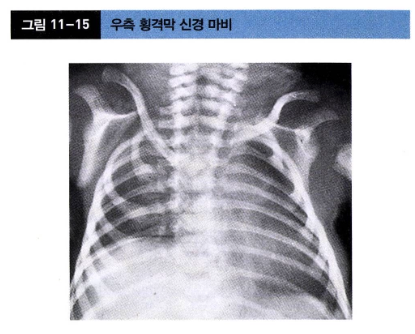

횡격막 신경 마비 (Phrenic Nerve Palsy)

• 원인: 횡격막의 운동을 지배하는 횡격막 신경(C3, C4, C5 신경근에서 기원)이 분만 중 견인 손상을 받아 발생함.

• 임상 양상

• 상완 신경총 마비, 특히 Erb 마비와 동반되는 경우가 많음 (약 75%).

• 호흡 곤란이 주 증상

• 특징적으로 숨을 들이쉴 때 마비된 쪽 횡격막이 위로 올라가고 건강한 쪽은 내려오는 seesaw 운동이 관찰

• 진단 및 치료

• 진단은 흉부 X-ray나 초음파 검사를 통해 마비된 쪽 횡격막의 상승 및 움직임 저하를 확인하여 이루어짐.